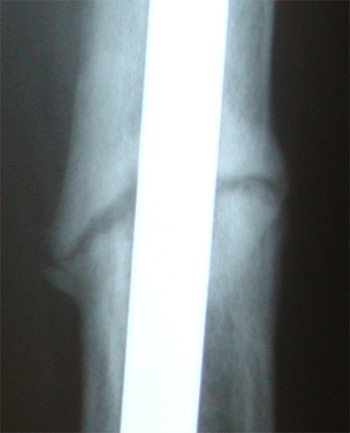

Anterior view of x-rays. Week 6 post op, Nov. 16, on left. 3 months (current) on the right.